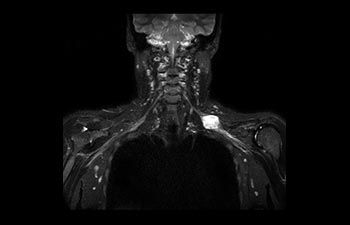

Encuentre la aplicación clínica adecuada a sus necesidades